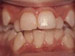

Overbite: Protruding front teeth